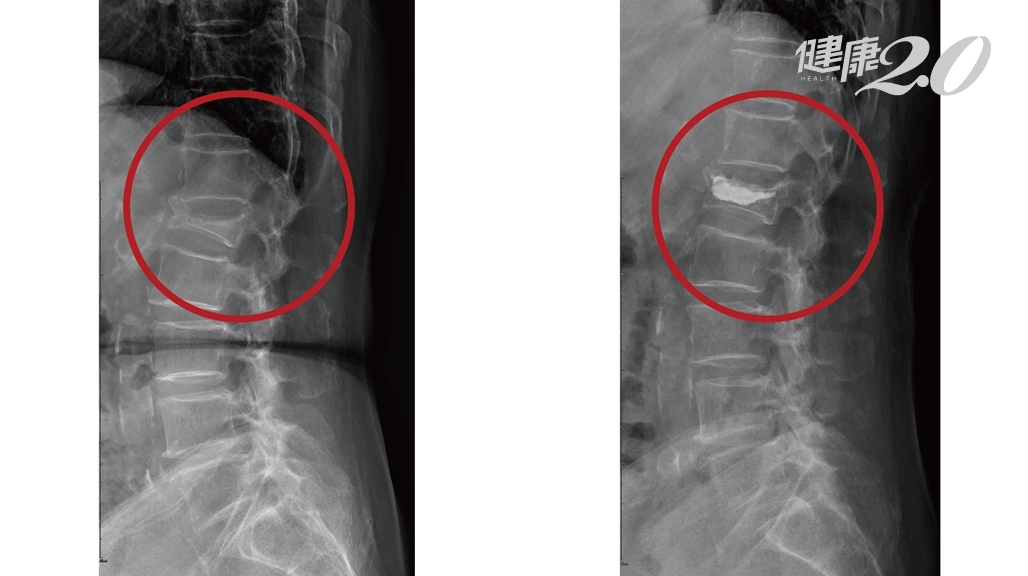

張偉德醫師說明,針對壓迫性骨折,X光的檢查是最基本的,尤其是一系列的X光記錄,比如每星期照一次做比對,可以發現脊椎的椎體變成楔狀(Wedge shape),也就是椎體的高度減少了,時間久一點甚至椎體裡還會出現空氣,就是告訴我們骨折沒有癒合,而且仍然處在不穩定的狀態。

▲病人經由「椎體成形術」找回健康,左圖為手術前、右圖為手術後。